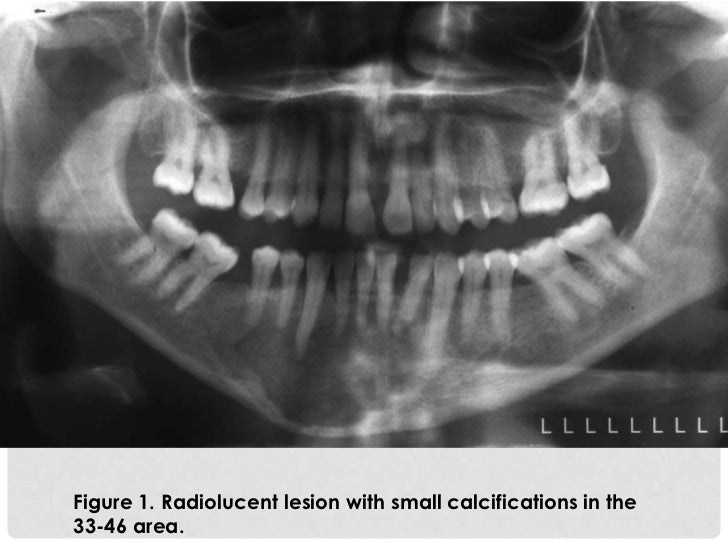

Osteoid Osteoma of the Mandible Clinical and Histological Findings Osteoma Oral Tratamiento La tomografía computarizada ayuda a delimitar el tamaño del tumor y su relación con las estructuras adyacentes.1,2,5 histológicamente. El presente estudio reporta el caso de un osteoma periférico aislado en un paciente de sexo masculino, de 30 años, localizado en la región del ángulo mandibular izquierdo. Three cases were managed through extra oral submandibular approach; El osteoma es una neoplasia. Osteoma Oral Tratamiento.